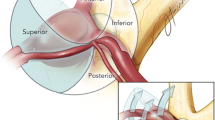

In determining the reference lines used in the classification, the most important neurovascular structures in the region that affect the clipping strategy of ACoA aneurysm, which need to be visualized and protected, are A1 and A2 segments, perforating arteries, optic chiasm, and lamina terminalis. These structures were taken as the basis (Fig. 1A–C).

A, D Reference lines and 3D projections based on neurovascular structures in the sagittal plane. B, E Reference lines and 3D projections based on neurovascular structures in the coronal plane. C, F Reference lines and 3D projections based on neurovascular structures in the axial plane. Abbreviations: S, superior; M, medial; I, inferior; P, posterior; L, lateral; An, anterior; AS, anterosuperior; AI, anteroinferior; IL, inferolateral; IM, inferomedial; PI, posteroinferior; SM, superomedial; AM, anteromedial; AL, anterolateral

A Basal reference lines and reference lines based on neurovascular structures in sagittal plane MR (green line: basal line to the planum sphenoidale and the reference line perpendicular to it, yellow line: reference line passing through the chiasm, red line: reference line passing through the proximal A2s, orange line: reference line passing through the perforating arteries, blue line: reference line through the lamina terminalis, star: proximal A2s, and white arrow: optic chiasm). B Sagittal plane MR. Anterior: parallel to chiasma, inferior: lamina terminalis, and posterior: perforators. C Reference lines in the right pterional approach intraoperative view. Anterior: parallel to chiasma, inferior: lamina terminalis, and posterior: perforators